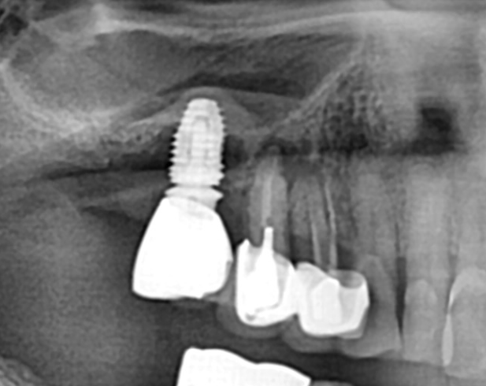

타원 실패 임플란트 재 시술 증례.

Before

모든 것은 영구적일 수 없습니다.

임플란트도 각종 합병증이 생길 수 있고 본 케이스 처럼 잇몸 뼈가 70~80%이상 소실 되면

제거하고 다시 시술해야 할 수 있습니다.

잇몸 뼈가 많이 소실된 상태이므로 임플란트 재수술은 보통 더 어려울 수 밖에 없습니다.